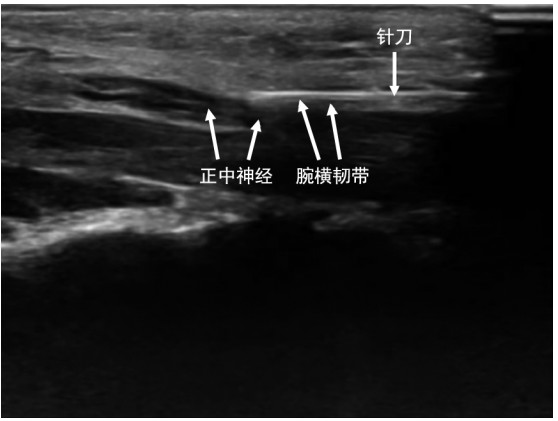

Comparison of the efficacy of ultrasound-guided acupotomy visualization and traditional blind acupotomy in the treatment of carpal tunnel syndrome

ZHANG Li, YANG Mei, WANG Yuan, DU Fenfei

2025, 23(9): 1569-1572. doi: 10.16766/j.cnki.issn.1674-4152.004179

367 3

Abstract:

Objective  Ultrasound visualization provides technical support for the precise application of acupotomy in treatment of carpal tunnel syndrome (CTS). This study explores the application advantages of ultrasound-guided acupotomy in the treatment of CTS compared with traditional blind acupotomy.  Methods  A total of 94 patients with CTS who received acupotomy therapy at the Department of Rehabilitation in Dongyang People ' s hospital from January 2022 to February 2025 were enrolled. According to different treatment methods, they were divided into a control group (receiving traditional blind acupotomy therapy) and an ultrasound group (receiving ultrasound-guided acupotomy therapy), with 47 cases in each group. They were both received twice treatment sessions and followed up for 4 weeks. Pain visual analogue scale (VAS) scores, ultrasonic measurements [thickness of transverse carpal ligament (TTCL), median nerve cross-sectional area (CSA), and anterior and posterior diameter of median nerve (D) in the cross section of uncinate bone], EMG measurements [median nerve end motor latency (DML), median sensory nerve conduction velocity (SNCV), and compound muscle action potential (CMAP)] were compared between the two groups before and after treatment. Pre- and post-treatment comparisons were performed to evaluate the therapeutic efficacy and the complications.  Results  The VAS scores of numbness and pain in daytime and nighttime after treatment were lower than those before treatment (P < 0.05). In addition, the daytime [(2.04±0.61) points vs. (2.61±0.70) points] and nighttime numbness VAS scores [(2.23±0.64) points vs. (2.87±0.75) points] of the ultrasound group were lower than those of the control group (P < 0.05), respectively. After treatment, TTCL, CSA, D, and DML were significantly decreased, while SNCV and CMAP were higher than before treatment (P < 0.05). Improvements were more pronounced in the ultrasound group than in the control group, while SNCV and CMAP were higher than control group (P < 0.05). The therapeutic grade composition of the ultrasound group was better than that of the control group (Z=4.506, P=0.003), with no significant difference in the complication rates between the two groups (P>0.05).  Conclusion  Compared with traditional blind acupotomy, ultrasound-guided acupotomy provides better symptoms relief of numbness and pain in CTS patients, improves the ultrasonography and EMG indicators, and improves clinical efficacy.